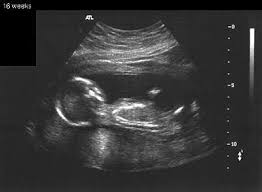

الجنين في الاسبوع العاشر من الحمل

كيف يكون شكل الجنين في الاسبوع السابع بالسونار 3a2ilati

الجنين في الاسبوع السابع بالسونار